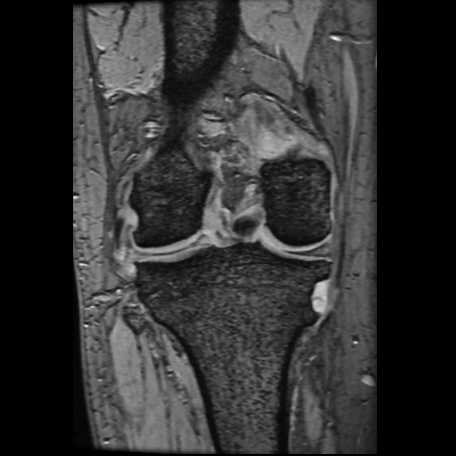

膝関節

半月板損傷